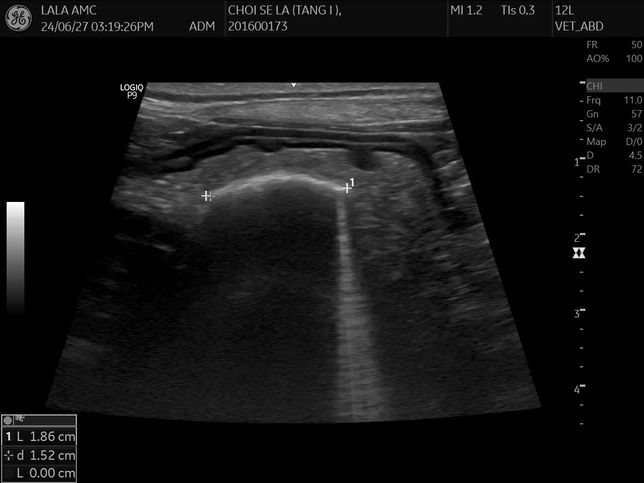

- 반려동물 건강반려동물Q. 강아지 몸속에 1.8cm물체가 있는것 같다는데 뭔지 모르겠어요건강검진 하면서 초음파를 찍었는데 강아지 몸속에 1.8cm 물체인지 뭔가가 보인다고 합니다 건강검진은 아무이상 없었구요의사선생님은 괜찮을것 같다고 했는데그리고나서 갈색토를 했구요 오늘아침에는 묽은변을 봤어요 (활력좋구요 사료먹는거 배변하는거는 이상없었습니다)자세한건 내시경을 해야한다고하네요..저것만봐서는 물체가 있는것같나요?엑스레이도 찍었는데 엑스레이로는 안보이는것같아요